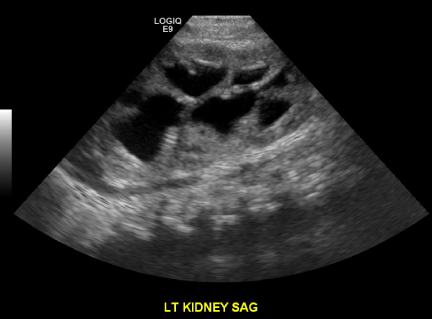

Ultrasound performed on the first day of life demonstrated bilateral hydronephrosis with a distended mildly trabeculated bladder (Figures 3-5). Both testicles were found in the inguinal canals. VCUG performed on day of life one revealed massive bilateral vesicoureteral reflux with intrarenal reflux. There were bilateral giant bladder diverticula, corresponding to the sonolucent structures adjacent to the bladder felt to be urinomas or enlarged ureters on prenatal examination (Figure 6). The posterior urethra was only mildly dilated with a gaping patulous bladder neck (Figure 7). There was also filling of a normal appearing prostatic utricle (Figure 7).

Ultrasound on POD # 2 revealed improved bilateral hydronephrosis, bladder diverticula and a trabeculated bladder (Figures 9 and 10).